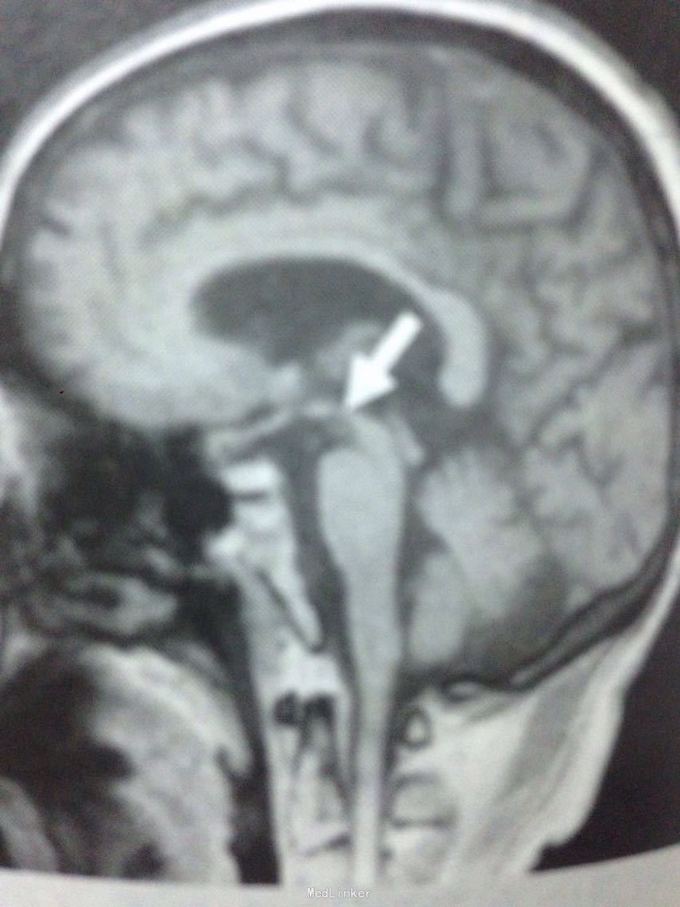

查体:神智清楚,对答切题,言语不清,双眼球上视、下视明显障碍,四肢肌张力偏高,余查体未见明显异常。 门诊头颅CT示:脑萎缩,脑白质变性。 颅脑MR示:T1矢状位中脑上部呈鸟嘴状改变,整体影像符合进行性核上性麻痹表现。

诊断为进行性核上性麻痹(PSP)。 治疗上予美多芭,VB6,辅酶Q10,控制血压等治疗。